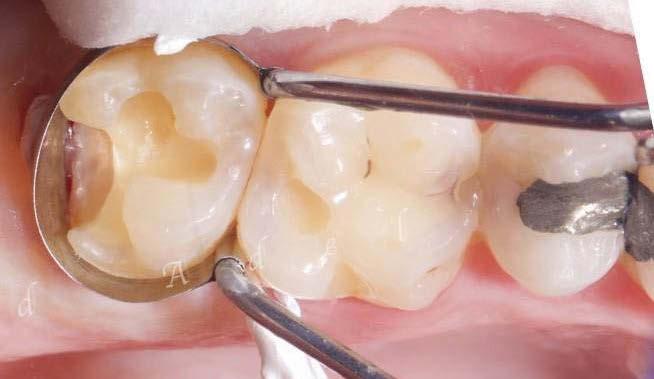

Exploración Intraoral

Presenta un estado oral deficitario. Parcialmente edéntula, con colapso de mordida, migración dental patológica, restauraciones de resina antiguas fisuradas y filtradas, transparencia y exposición de cámara pulpar secundaria a desgastes con pérdida de estructura e integridad de tejido dental importante (Figuras 1 a 4). Portadora a tiempo parcial de prótesis removibles desadaptadas de más de 10 años de antigüedad, refiriendo incapacidad de adaptación a este tipo de prótesis.